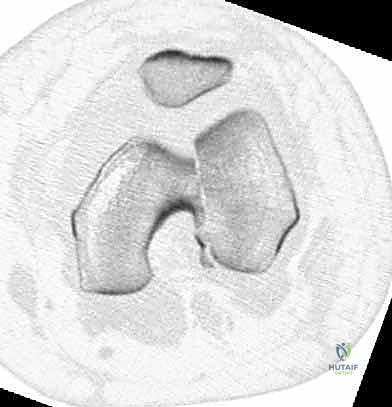

- الأشعة السينية (X-Rays): أخذ صور من زوايا متعددة (أمامي خلفي، وجانبي) لتحديد موقع الكسر ونوعه.

- الأشعة المقطعية (CT Scan): وهي ضرورية جداً في كسور عظم الفخذ البعيدة، خاصة إذا كان الكسر يمتد إلى داخل مفصل الركبة (Intra-articular fractures). تساعد الأشعة المقطعية الدكتور هطيف على بناء نموذج ثلاثي الأبعاد للكسر، مما يسهل التخطيط الجراحي وتحديد أماكن وضع المسامير بدقة.